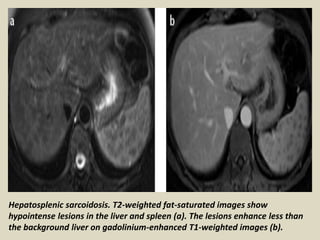

Hepatosplenic sarcoidosis. T2-weighted fat-saturated images show

hypointense lesions in the liver and spleen (a). The lesions enhance less than

the background liver on gadolinium-enhanced T1-weighted images (b).